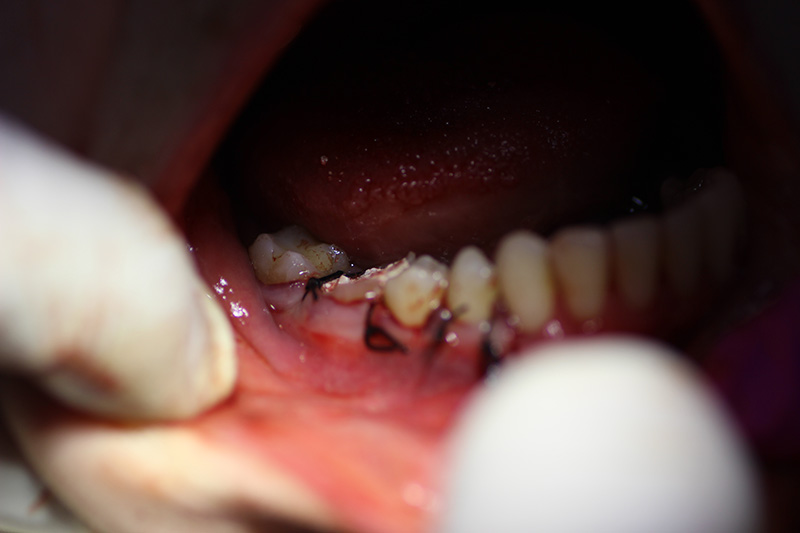

The patient underwent an operation of apicotomy (resection of the apex of the tooth root) and removed the cyst.